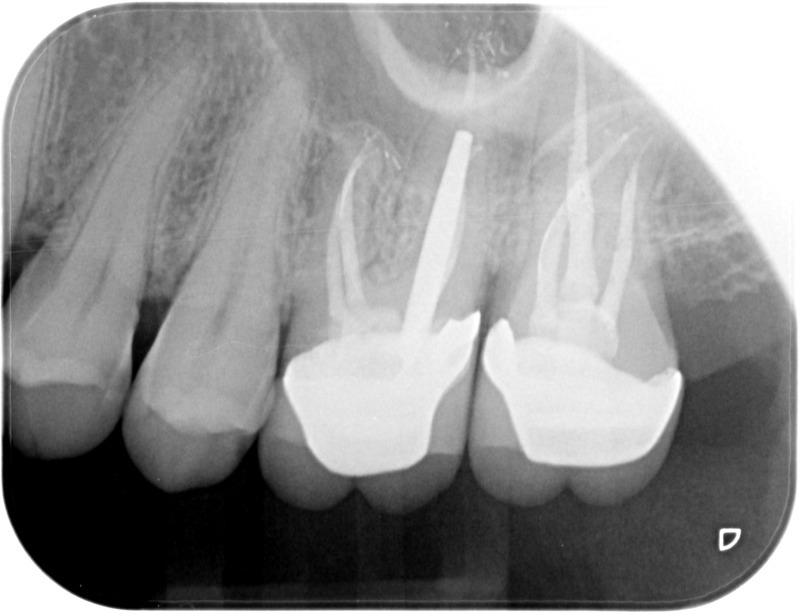

• Traitement endodontique : Sous anesthésie locale et à travers la protection d’un champ opératoire nous accédons à la pulpe de la dent à soigner, puis aux canaux de ses racines que nous devons désinfecter. Ce soin nécessite l’élimination complète de la source de contamination (souvent la carie) parfois sous une ancienne reconstitution ou une couronne qu’il faut alors retirer. Une fois le nettoyage et la mise en forme des canaux réalisés, nous les obturons de façon hermétique avec un ciment et un matériau thermoplastique appelé Gutta Percha. Ceci afin d’empêcher une nouvelle prolifération bactérienne et d’assurer le maintien de la dent dans ses structures de soutien (ligament parodontal et os alvéolaire). L’ouverture effectuée au centre de la dent sera d’abord refermée avec un pansement provisoire avant d’envisager ensemble la reconstitution d’usage : un composite, un inlay-onlay ou une couronne.

Avant

Après